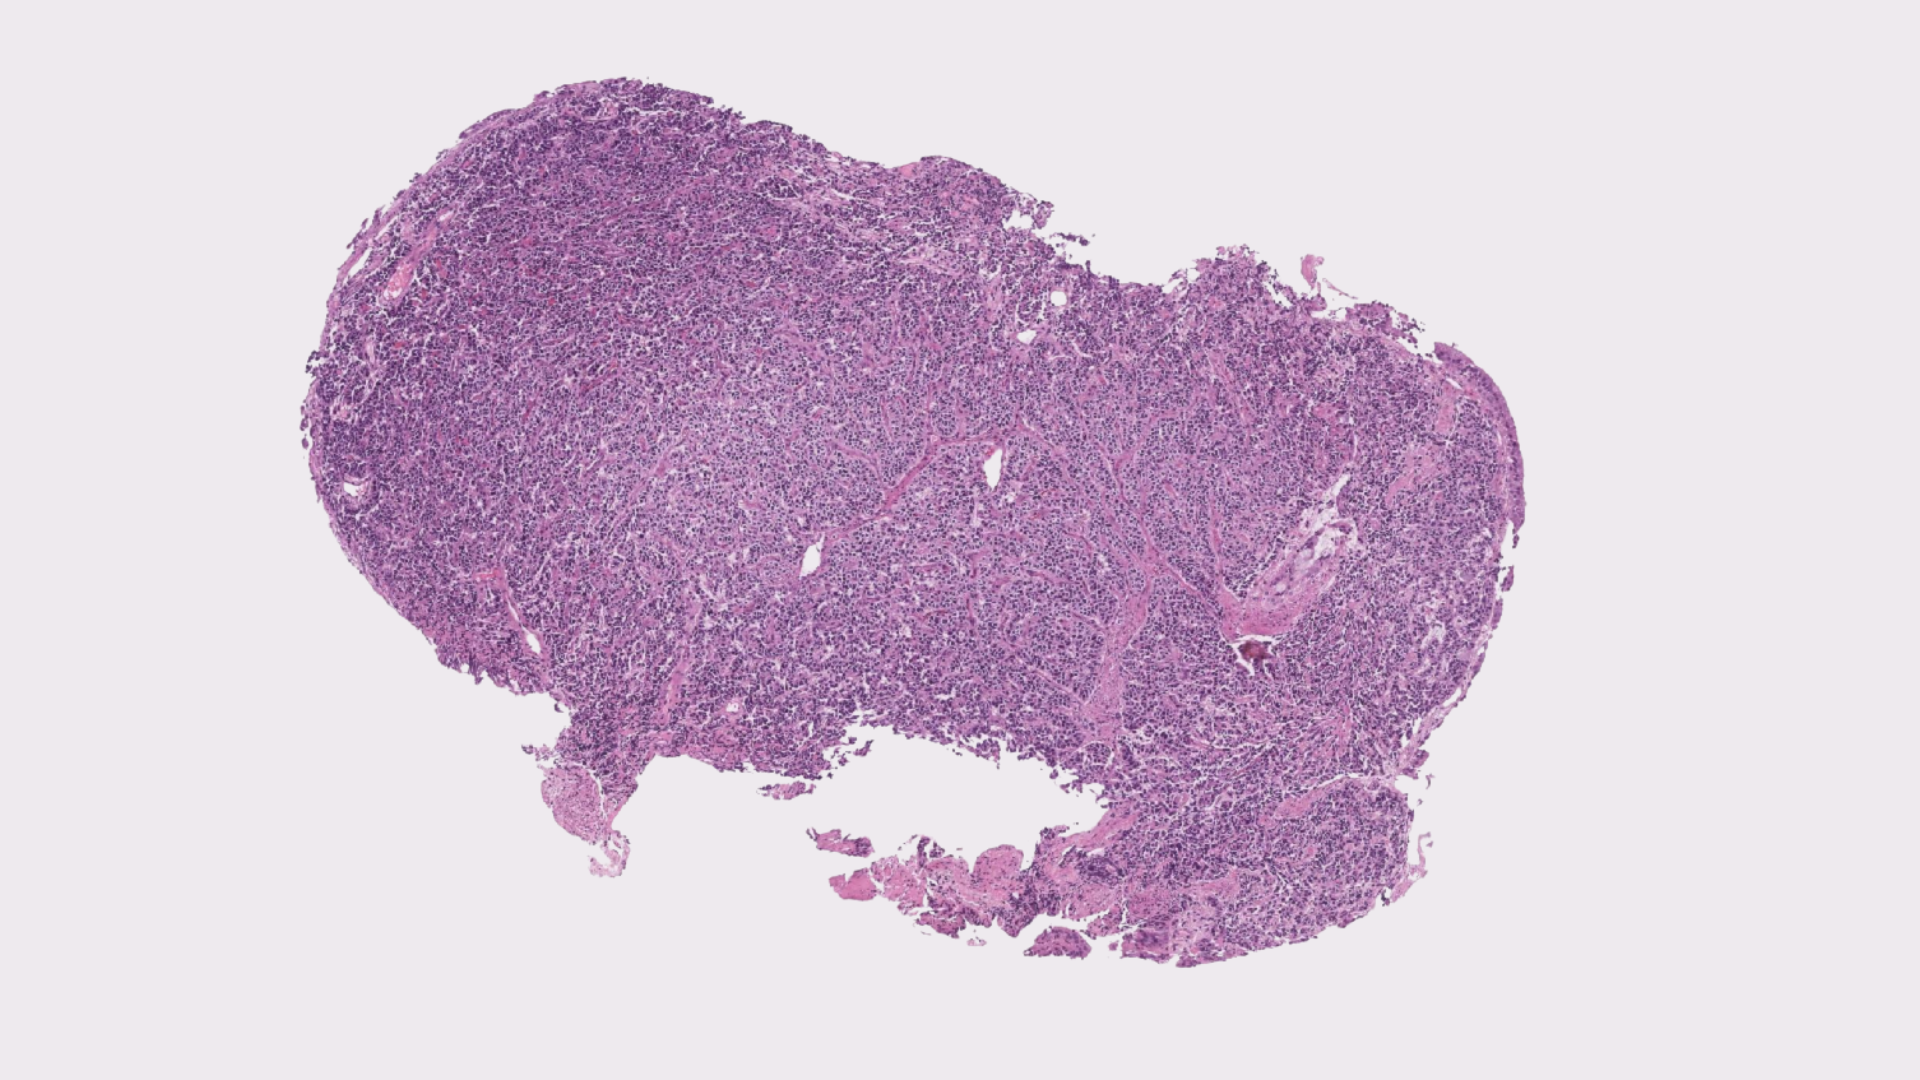

Endogenous fluorophores are naturally occurring molecules within tissue that emit fluorescent signals when excited by specific wavelengths of light. These signals provide intrinsic structural contrast without the need for chemical dyes. Pictor Labs captures this autofluorescence signal to generate high-resolution images of unlabeled tissue samples.

The captured autofluorescence image is processed through a deep learning model trained on paired, unstained and conventionally stained tissue samples. Through image registration and feature mapping, the model learns the relationship between intrinsic tissue signals and their corresponding histologic appearance.

During model training, autofluorescence images are co-registered with matching brightfield images obtained after conventional staining. This alignment enables the model to learn how unstained tissue features correspond to traditional histologic stains such as H&E or IHC. During inference, the trained model applies this learned transformation to new, unstained tissue images, generating virtual stains that visually replicate conventional microscopy. Because tissue is not chemically altered, multiple computational stain transformations can be applied to the same sample.